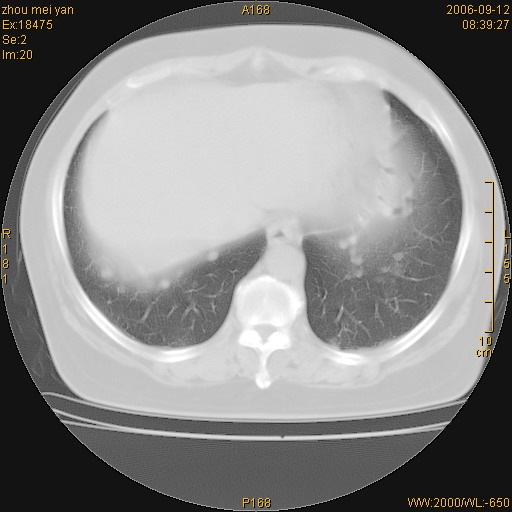

患者、女、55岁。因心率失常住院检查ct发现胸部多发结节。腹部b超肝、胆、胰、脾、肾、子宫附件未见异常。无结核病史,无粉尘接触史。请大家来会诊。谢谢!

病变位于胸膜,多发结节,边界清楚,内见小结节状钙化。其它未见异常。

双侧胸膜多发结节,形态不规则,边缘较清楚,每一个结节中心似乎都有钙化点的特征,与胸膜广基相切。临床无结核病史,无粉尘接触史。

影像表现十分有特点:双侧肋胸膜及膈胸膜广泛散在分布大小在2至6mm左右,较大病灶中心可见钙化。

双侧肋胸膜及膈胸膜广泛散在分布大小不等结节影,较大病灶中心可见钙化。